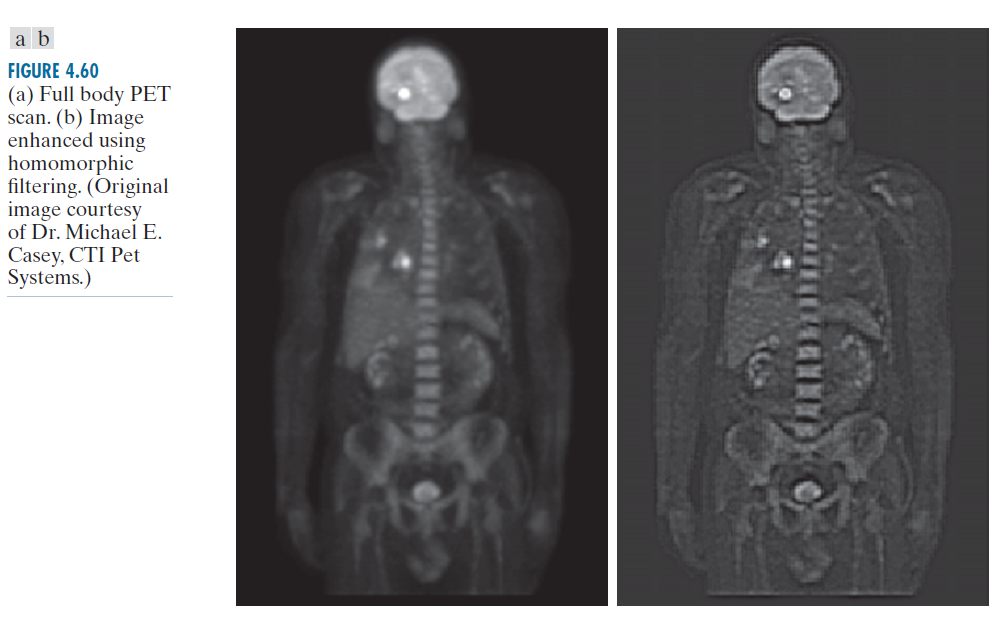

例子 4.23:同态滤波。

图 4.60(a) 显示了 1162 × 746 像素的全身 PET(正电子发射断层扫描)扫描图像。图像略显模糊,许多低强度特征被占据显示屏动态范围的"热点"的高强度信号所掩盖。(这些热点是由脑肿瘤和肺肿瘤引起的。)图 4.60(b) 是通过对图 4.60(a) 进行同态滤波获得的,使用公式 (4-147) 中的滤波器转移函数,其中 。该函数的径向横截面与图 4.59 非常相似,但斜率更陡峭,低频和高频之间的过渡更接近原点。

--------------------------图 4.60:(a)全身 PET 扫描。(b)使用同态滤波增强的图像。(原图由 CTI Pet Systems 的 Michael E. Casey 博士提供。)--------------------------